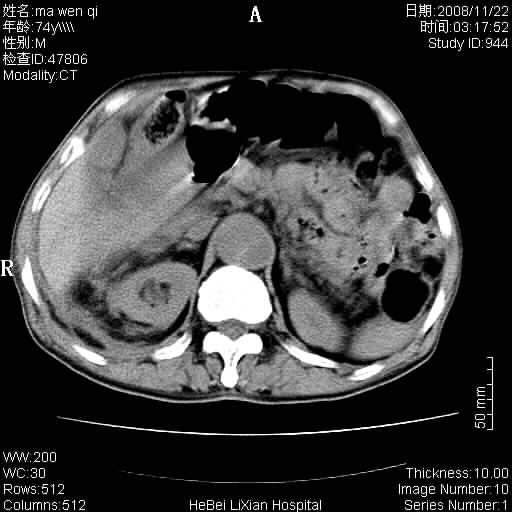

患者男 74岁.突然昏迷,休克6小时.血压70/30,头颅ct未见异常,既往体健.

补充病史,保留导尿10小时,尿袋内只有少许尿液,患者于住院后15小时后去世.

腹主动脉、双侧髂动脉夹层动脉瘤破裂出血进入腹腔。

1)考虑双侧髂动脉瘤并右侧动脉瘤破裂出血,右侧腹膜后及腹腔积血。2)双侧腹股沟疝。

1)考虑,腹主动脉、双侧髂动脉夹层动脉瘤破裂伴右侧腹膜后及腹腔积血。2)双侧腹股沟疝。

1)考虑胸、腹主动脉、双侧髂动脉瘤并右侧动脉瘤破裂出血,右侧腹膜后及腹腔积血。2)双侧腹股沟疝。